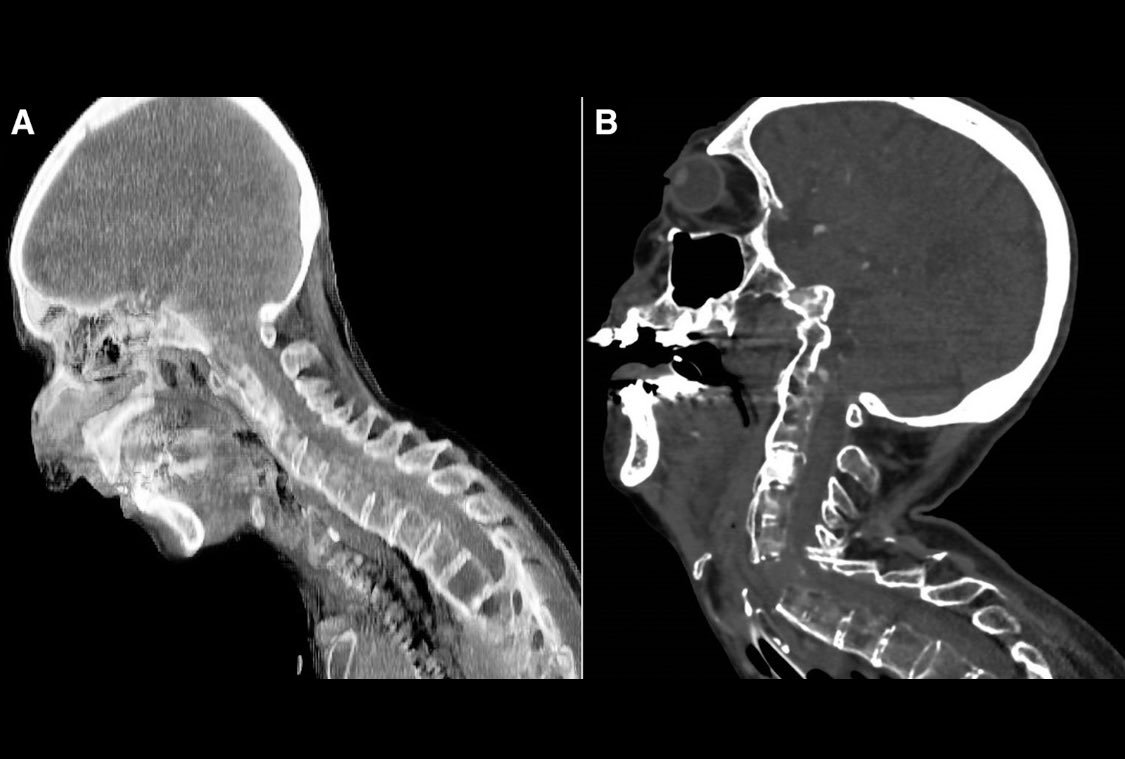

✨في حالة طبية نادرة تسمى (Ankylosing Spondylitis)، وهي مرض روماتيزمي مناعي مزمن يسبب التهاباً وتصلباً في العمود الفقري . تصور لما العمود الفقري يتحول إلى قطعة واحدة صلبة وفاقدة للمرونة تماماً مثل قصب الخيزران.

✨القصة المؤلمة لسيدة تبلغ من العمر 82 عاماً، تعاني من هذا المرض منذ سنوات، دخلت لعملية جراحية. طبعا لتأمين مجرى الهواء أثناء العمليه قرر الفريق استخدام "المنظار الحنجري بالفيديو" (Video Laryngoscopy).

✨طبعاً التكنولوجيا لا تغني عن المهارات الأساسية وليست دائماً الحل! طبعا المنظار بالفيديو عادة ما يكون منقذاً في الحالات الصعبة، لكن في هذه الحالة، وبسبب الزاوية الحادة للمنظار والقوة التي استُخدمت لرؤية الأحبال الصوتية، حدث ما لم يكن في الحسبان.. "كسر!"

4/ الكسر كان بسبب القوة التي بُذلت لتوسيع مجرى التنفس تسببت في كسر الفقرات العنقية (C5-C6).

✨ تخيل أن رقبة المريض كُسرت أثناء محاولة إنقاذ حياتها بالتنفس! لأن الرقبة "الهشة" لم تتحمل أدنى ضغط لتعديل زاويتها.

✨الدرس القاسي في هذه الحالة المنشورة في مجلة Anesthesiology أصبحت مرجعاً عالمياً 💥الرسالة واضحة: في حالات "العمود الفقري الملتحم"، التكنولوجيا قد تخونك، واللطف والمهارة اليدوية الفائقة ومعرفة تاريخ مريضك المرضي جيدا أهم من أقوى الأجهزة.

✨الخلاصة: "القوة" لا تعني دائماً "السيطرة ". أحياناً، محاولة رؤية الحبال الصوتية تحت ضغط الوقت والخوف من تدهور الحالة قد تكلف المريض عموده الفقري. دائمًا اسأل عن البدائل الأكثر أماناً في الحالات المعقدة.